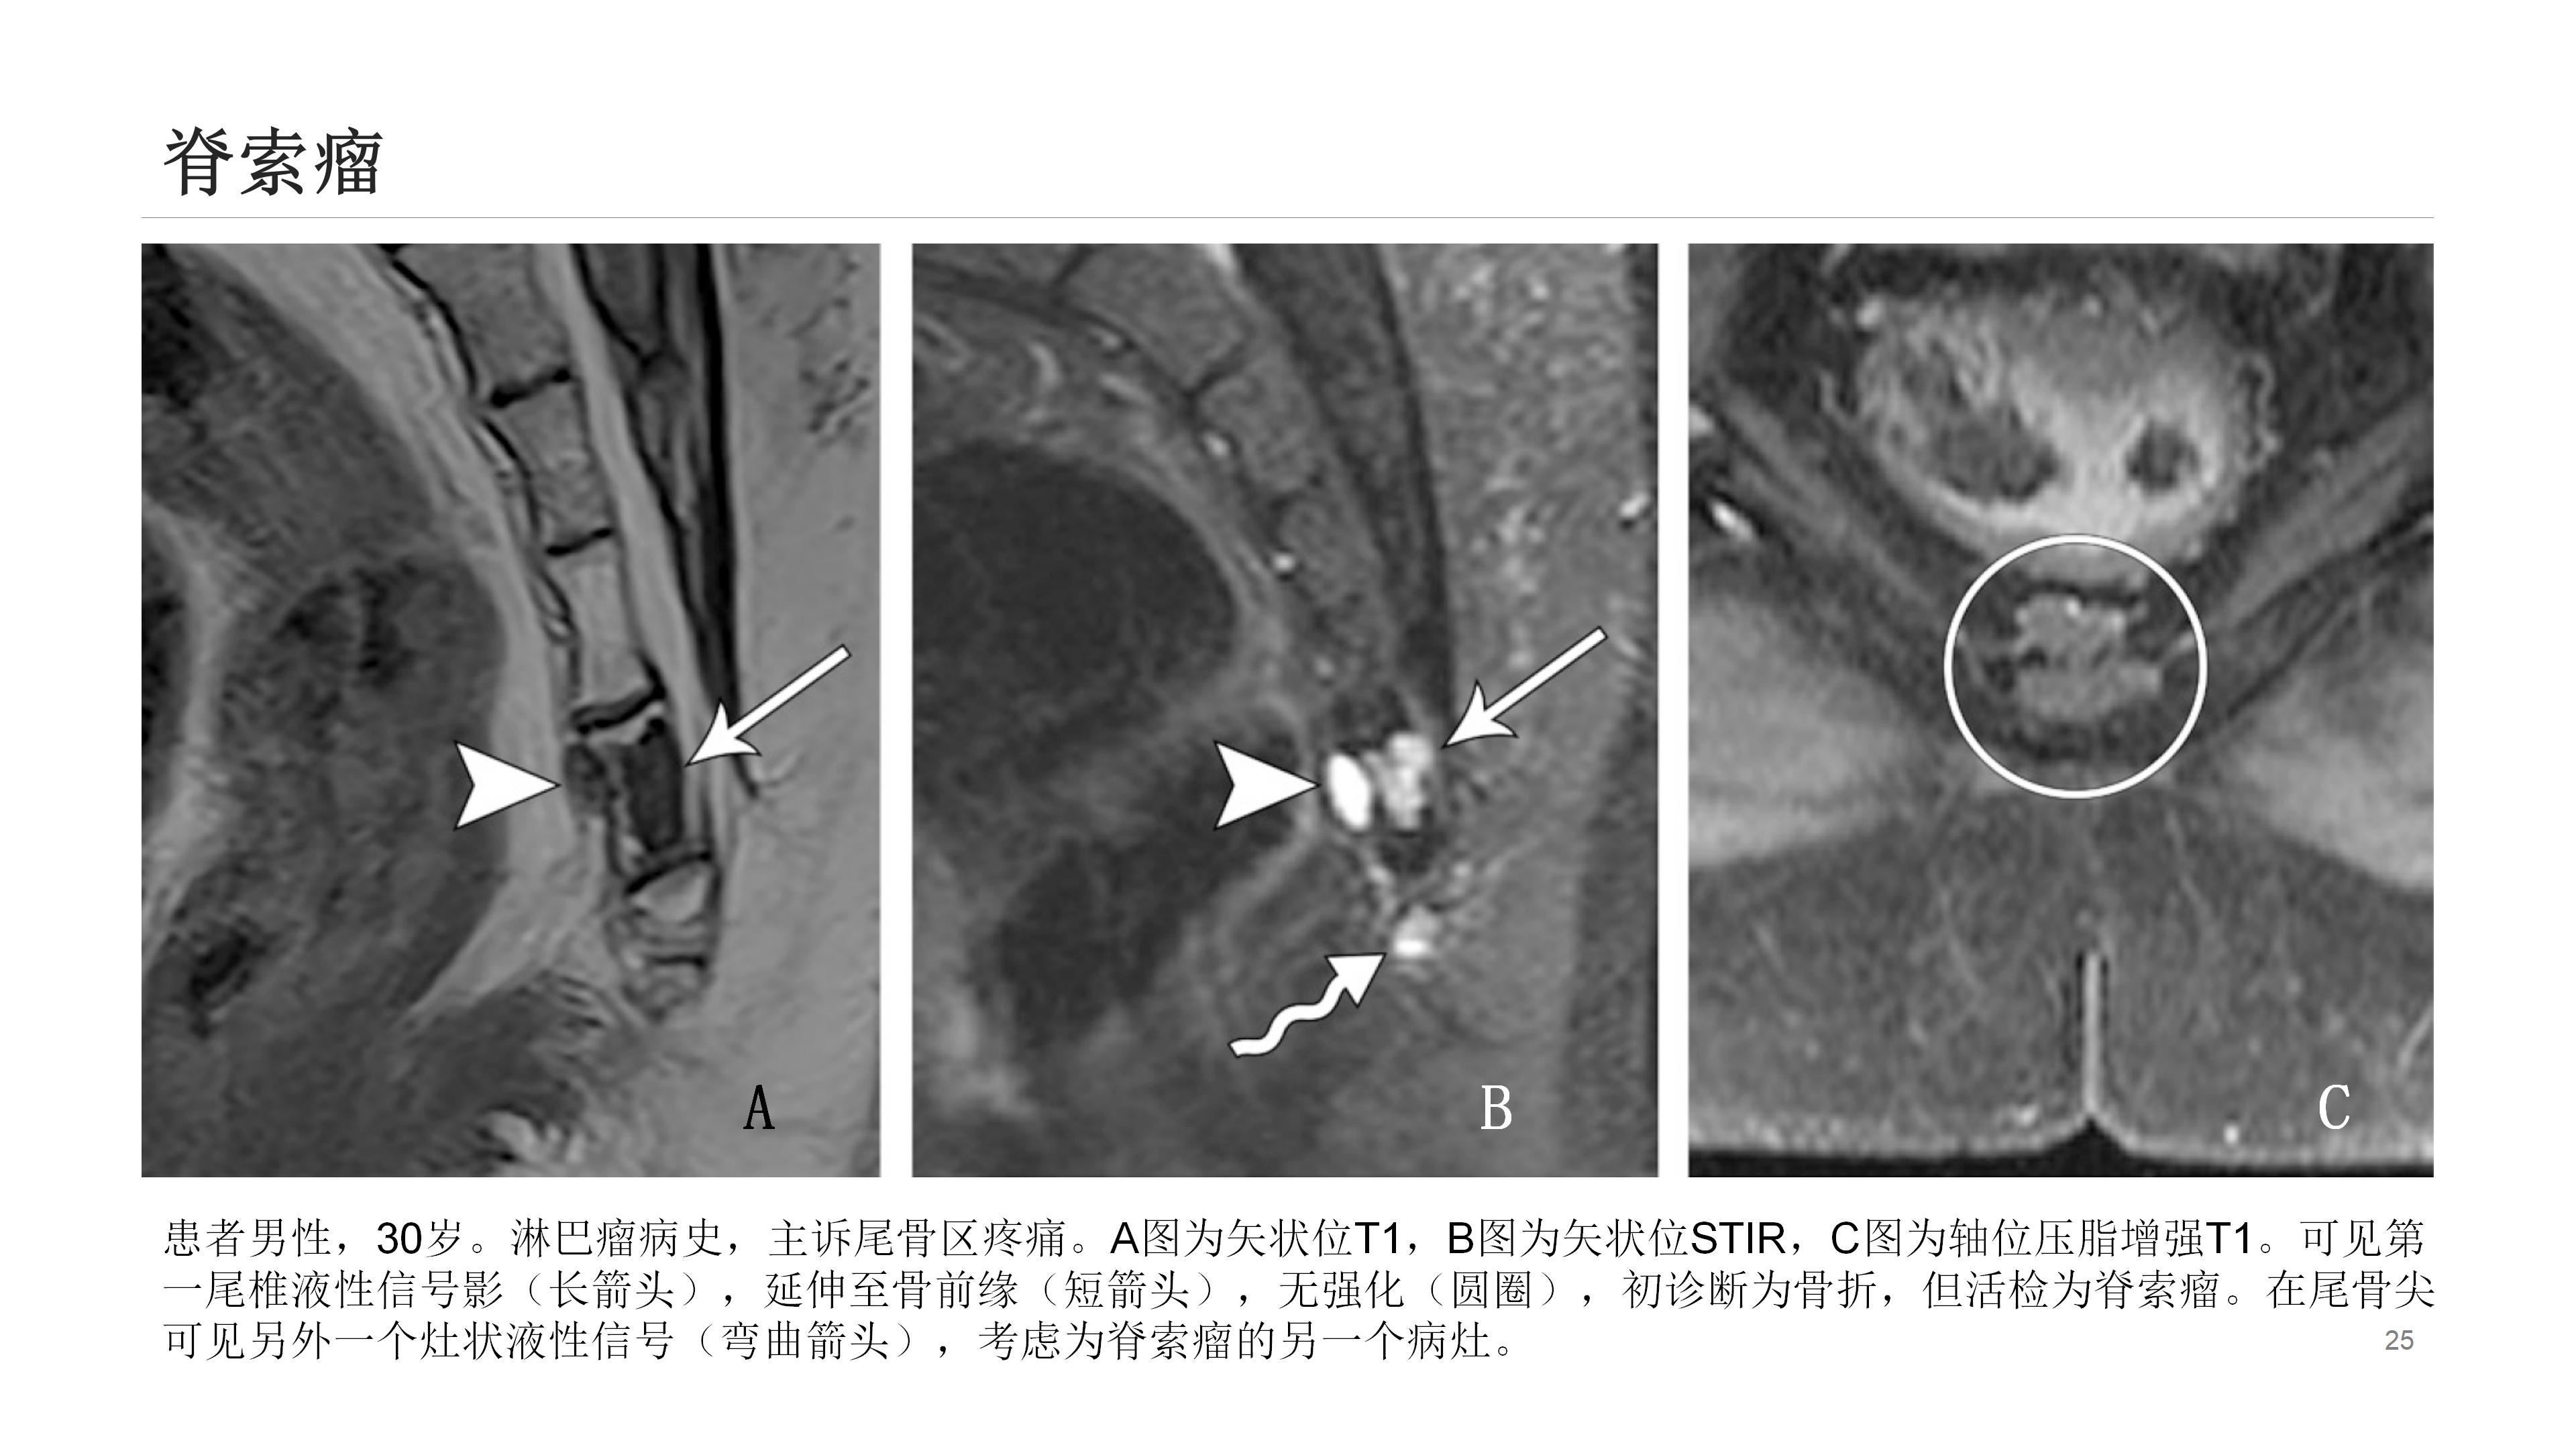

此外,诸如肿瘤、感染、晶体沉积病、囊肿形成(如藏毛囊肿)等其他疾病也可导致尾骨疼痛。